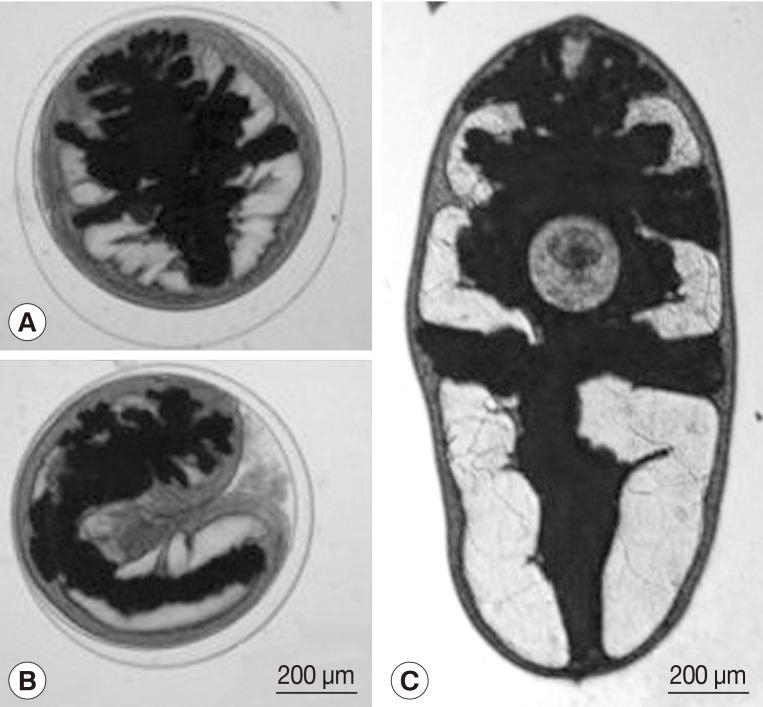

Paragonimus paishuihoensis Metacercariae in Freshwater Crabs, Potamon lipkei, in Vientiane Province, Lao PDR

The Korean Journal of Parasitology 2013;51(6):683-687.